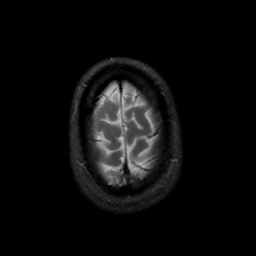

MR Study #22, December 1, 1991 -- Slice #45

[Home][Help][Clinical][Tour 1][Tour 2] Slice 45